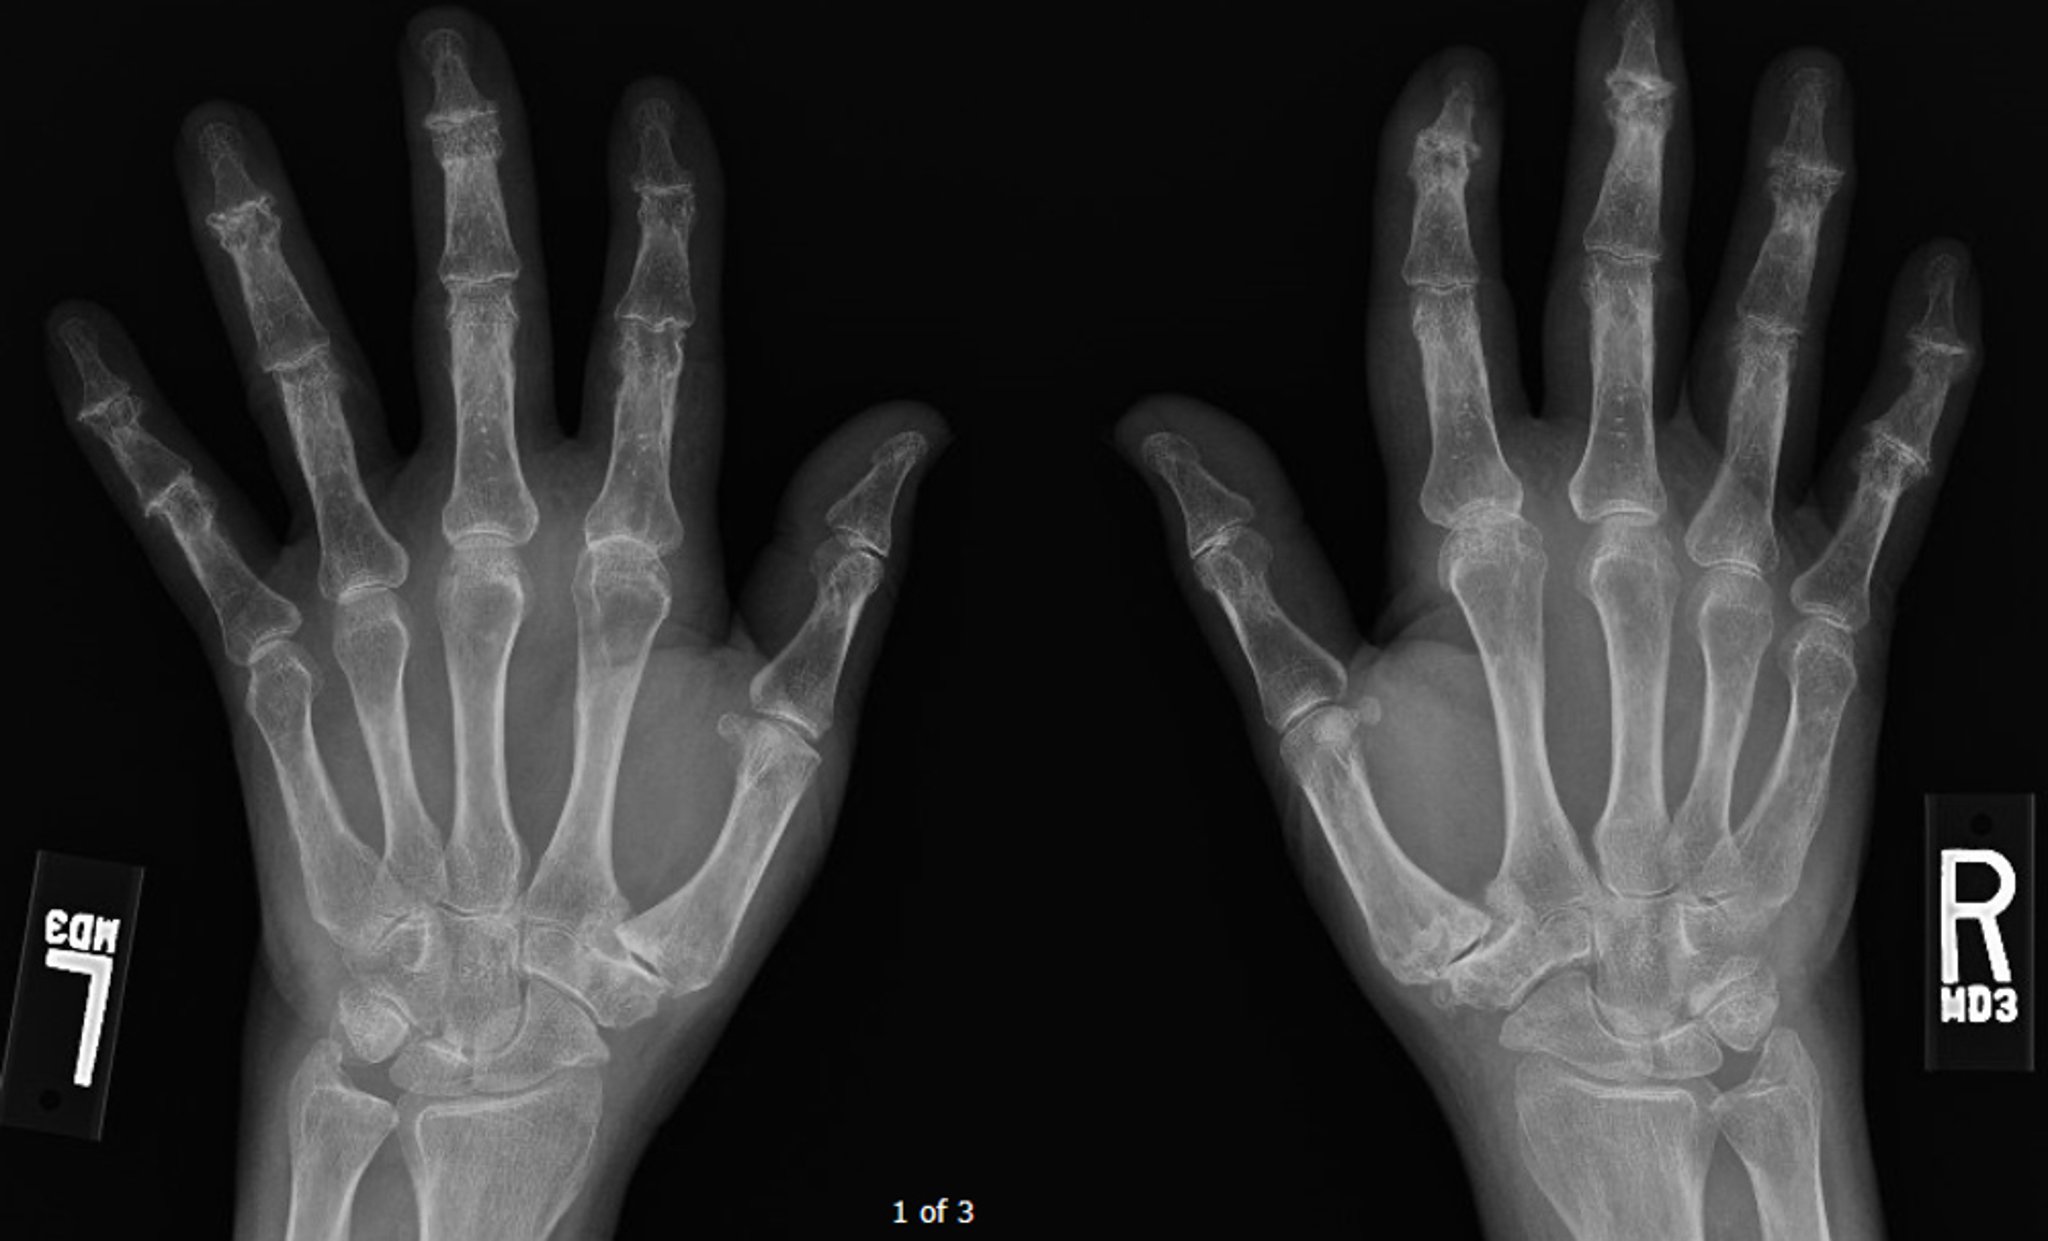

Erosive Osteoarthritis

This radiograph shows advanced diffuse osteoarthritis, most prominently at the distal interphalangeal joints, where some central erosions can be seen.

Image courtesy of Kinanah Yaseen, MD.